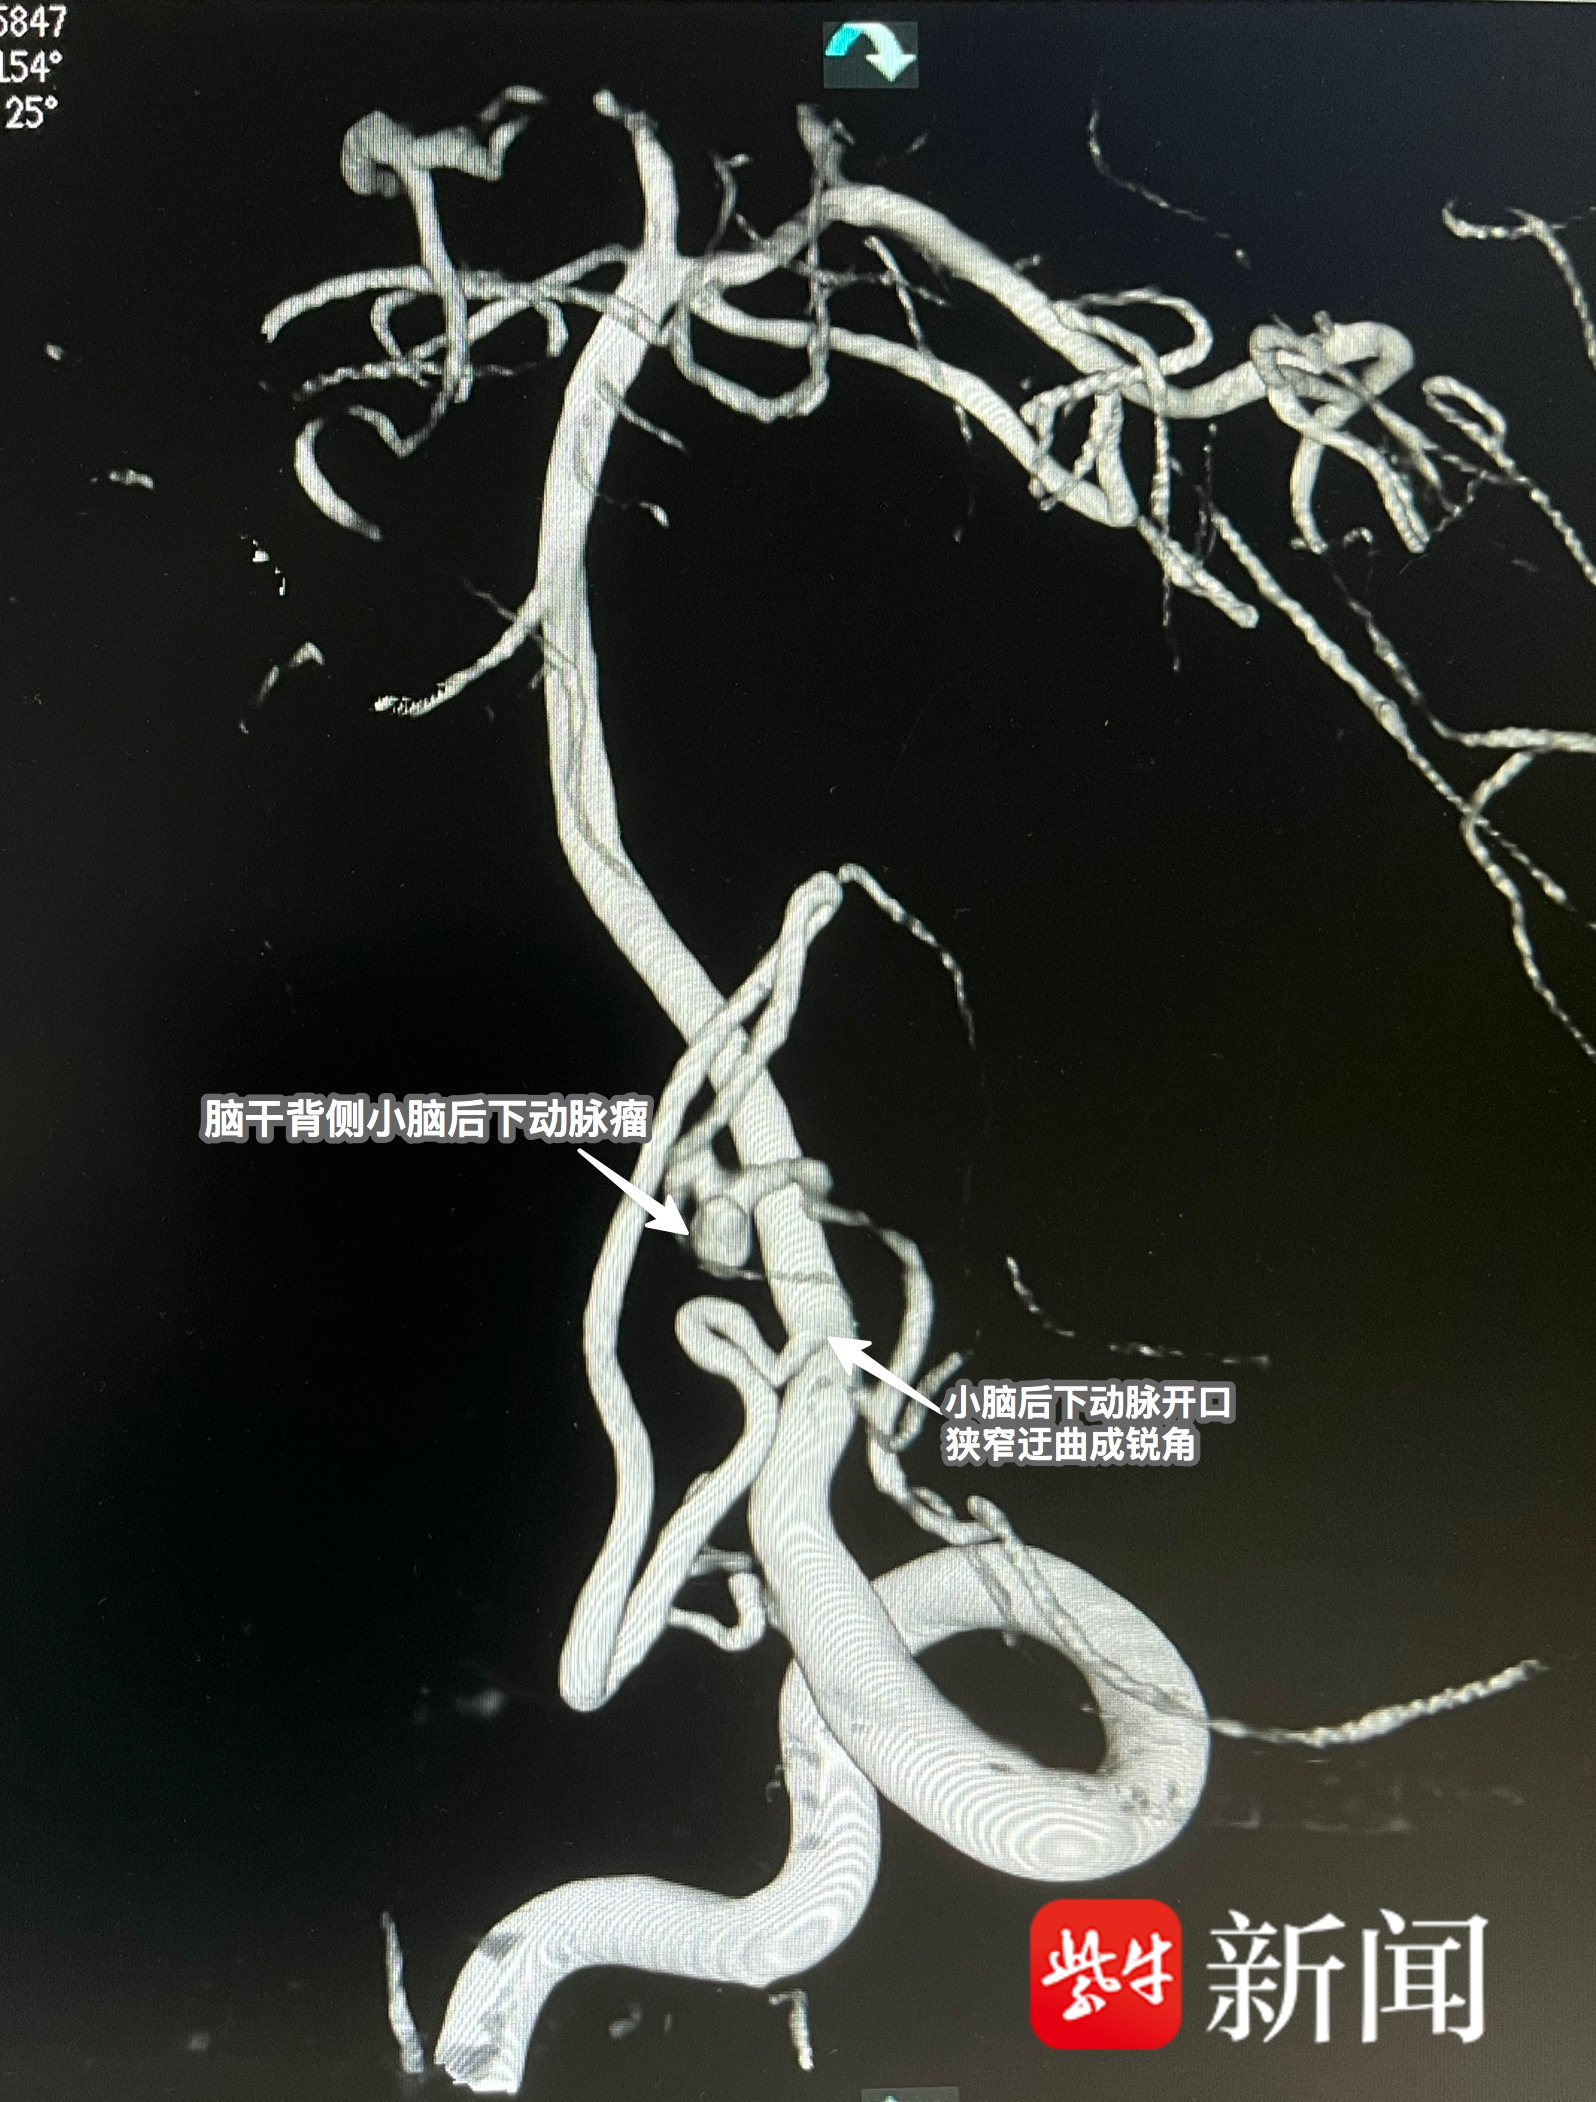

手术室内,生死竞速正式打响。马蓉副主任带领麻醉团队精准实施全麻,为手术筑牢安全防线;神经外科团队率先上阵,全麻后脑血管造影结果一出,在场医护人员顿时心头一紧——患者动脉瘤并非普通病变,而是位于脑干背侧、小脑后下动脉远端,血管开口狭窄、走行迂曲、成锐角发出,解剖结构极其复杂,栓塞难度远超预期,稍有不慎便会引发再次出血,危及生命!